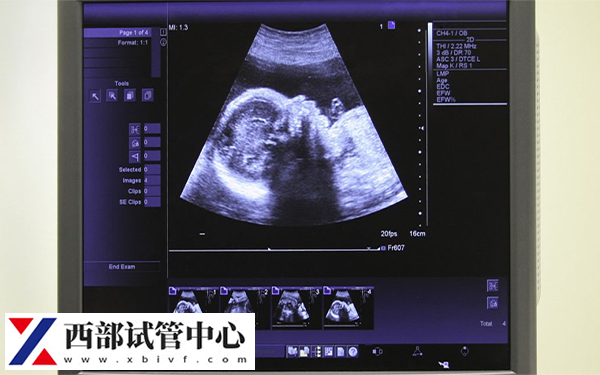

根据相关了解,FSH(促卵泡生成素)的水平是评估卵巢功能的重要指标之一,对于试管婴儿的成功率有显著影响。因此在fsh10.8的情况下,做是试管婴儿成功率并不是很高,数据可能只有30%-40%左右。

毕竟FSH值为10.8,略高于正常范围,可能表明存在一定的卵巢储备下降。这种情况下,试管婴儿的成功率可能会受到影响。然而具体情况建议以实际为准,毕竟充足的睡眠、健康的饮食结构、适度的运动等等,这些对于提高身体机能和改善卵巢功能都非常必要而有效。 因此可以在助孕之前进行身体调理。